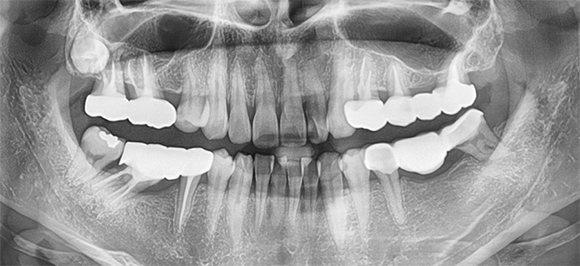

정확한 진단을 바탕으로 기능성과 심미성을 고려한 맞춤형

체계적인 시스템으로 철저한 관리 프로그램을 시행